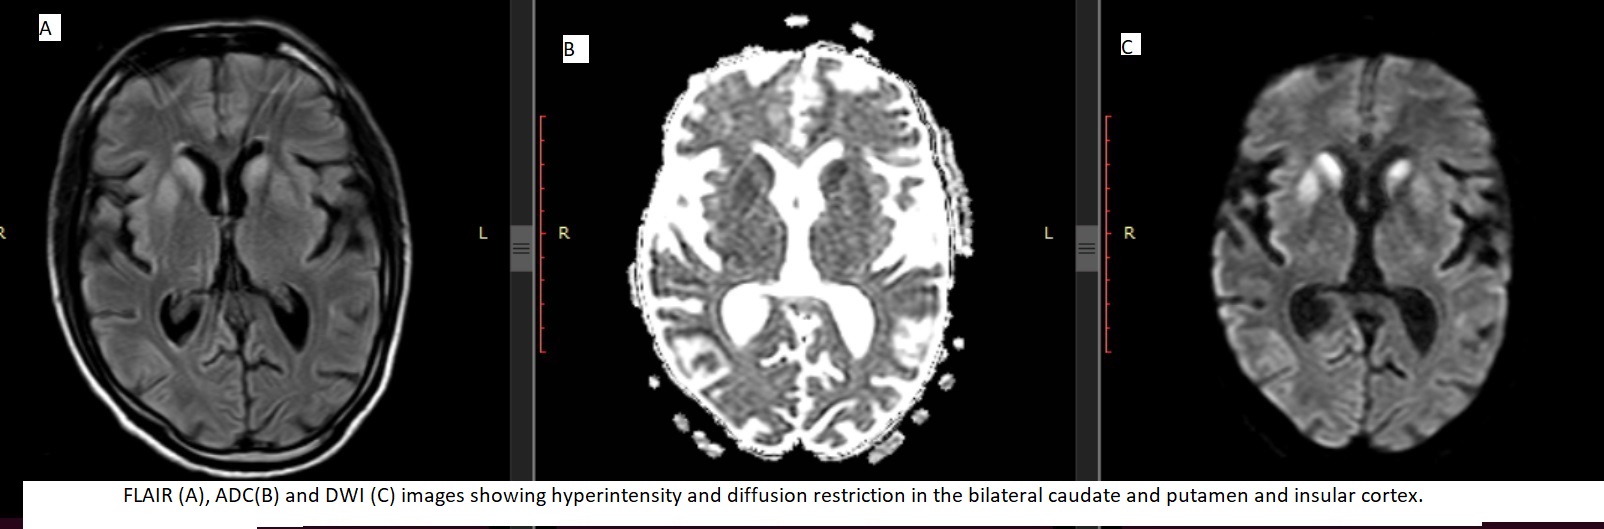

Results: EEG showed generalized slowing of background activity. However, no periodic sharp wave complexes are seen. FLAIR hyperintensity was seen in the superior frontal, middle frontal, orbital frontal, medial frontal, superior parietal, supra-marginal, angular, precuneus, superior temporal, middle temporal, inferior temporal, superolateral occipital, insula (anterior and posterior), superolateral occipital, cingulate (anterior and posterior), caudate and putamen. Diffusion restriction was also seen in the corresponding regions. MRI showed diffusion restriction on DWI/ADC images more than FLAIR hyperinetnsity in cingulate, striatum and more than 1 neocortical gyrus.

Fig.1